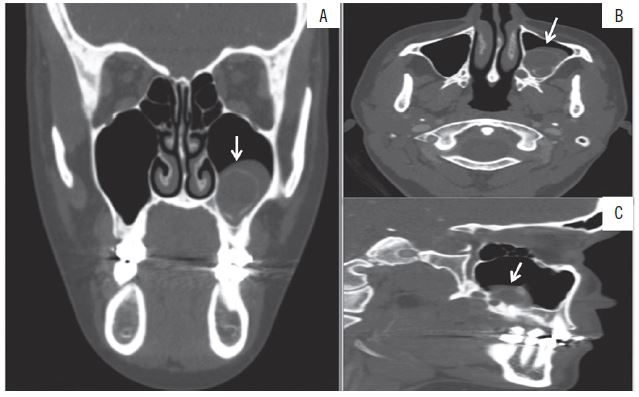

Clinical examination showed the absence of facial alterations and cervical lymphadenopathies. Intraoral examination revealed a swelling in the left posterior maxilla and pain on palpation (Figure 1). Computed tomography (CT) showed the presence of a hypodense lesion in the area of tooth 28 expanding to the maxillary sinus, but no cortical bone destruction (Figure 2).

A) coronal section; B) axial section; C) sagital section.

The main symptoms of intraosseous MEC are swelling, pain, trismus and paresthesia, depending on the size of the tumor(10,20). In the present study, the patient had a painful swelling in the posterior maxilla. Computed tomography detected a hypodense, unilocular lesion expanding to the cortical bones of the maxillary sinus, but no bone destruction was observed. These imaging findings led to the clinical diagnosis of odontogenic lesions, considering their higher incidence in this region(1,4,24,25). However, an incisional biopsy is important in the case of osteolytic lesions for histopathological, histological and immunohistochemical analyses that will establish the correct diagnosis.